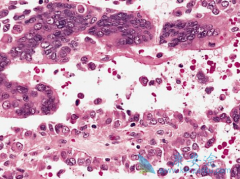

• 厄洛替尼(ERLOTINIB)联合阿瓦斯丁治疗EGFR突变的肺癌患者有效吗

厄洛替尼(ERLOTINIB)联合阿瓦斯丁治疗EGFR突变的肺癌患者有效吗

表皮生长因子受体酪氨酸激酶抑制剂(EGFR-TKI)可有效延长EGFR突变的晚期非小细胞肺癌患者的生存期,在EGFR突变的肺癌患者中,EGFR-TKI治疗前,可检测到高达65%患者伴有T790M突变,而T790M突变通常与缩短的PFS相关。BELIEF是一项II期单臂、多中心研究, ...